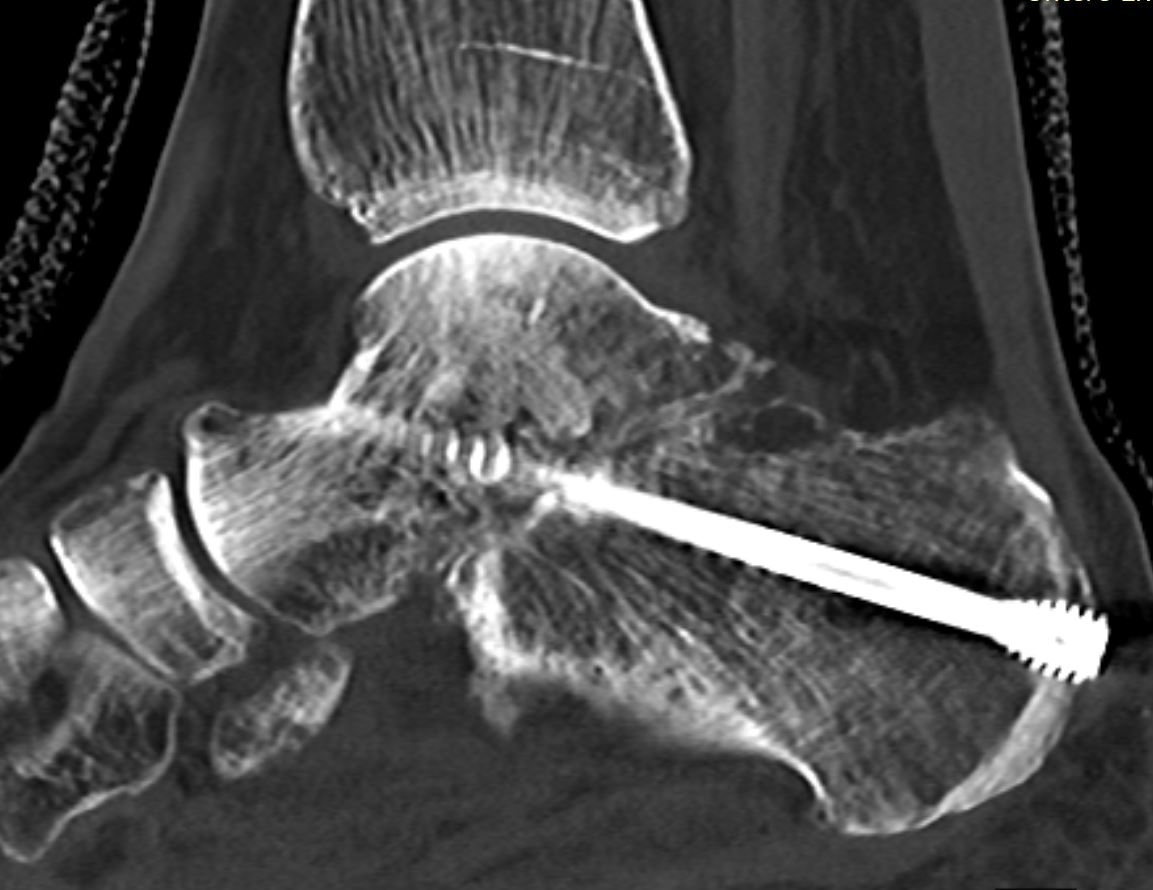

Home Schwerpunkte Krankheitsbilder Arthrose unteres Sprunggelenk USG Arthrodese 8 Wochen post OP subtotale Kopnsoliderung

USG Arthrodese 8 Wochen post OP subtotale Kopnsoliderung